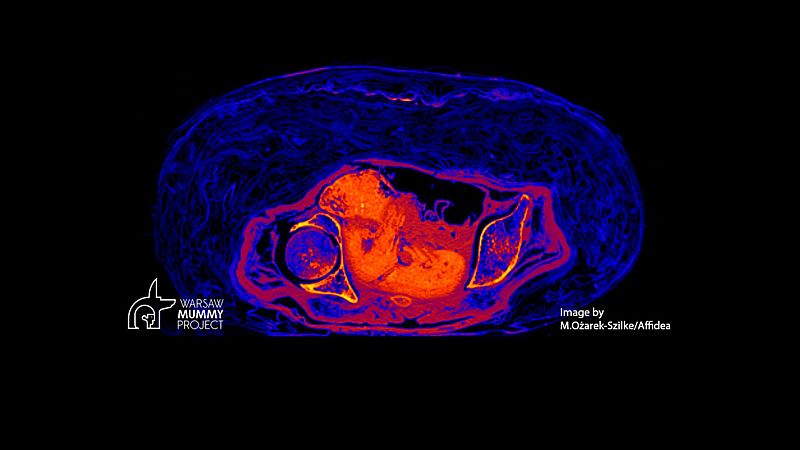

Imagen del feto de Warsaw Mummy Project

Científicos de la Universidad de Varsovia descubrieron el pasado mes de abril de 2021 un feto de 28 semanas intacto en el cuerpo de una momia egipcia. El increíble hallazgo llevó a los investigadores a preguntarse por la razón de su buena conservación, algo que ahora se ha revelado: la acidificación del cuerpo de la madre mientras se descomponía.

El feto, un caso sin precedentes, permaneció en el útero intacto y comenzó a "encurtir", según explica en un comunicado la arqueóloga y paleopatóloga Marzena Ozarek-Szilke, que lideró el equipo que halló la momia y que ha encontrado ahora explicación al inusual fenómeno.

Los resultados han descubierto que la colocación y llenado del cadáver limitaron significativamente el acceso de aire y oxígeno, con el resultado final de un útero casi herméticamente sellado. Así, el feto se encontraba en un ambiente comparable al que conserva cuerpos antiguos hasta nuestros días en los pantanos.

Como ha informado Ozarek-Szilke, se produjeron dos procesos de momificación diferentes. Mientras que el feto estaba en un ambiente ácido, "parecido a un pantano", que luego se secó durante el embalsamamiento de la madre, ella fue secada con natrón, un sodio natural en Egipto.

Asimismo, el cambio de un ambiente alcalino a ácido condujo a la descomposición parcial de los huesos fetales, señala el estudio publicado en Journal of Archaelogical Science. Los minerales de los huesos, que se disolvieron en el líquido amniótico, se depositaron en los tejidos blandos del feto y el útero.